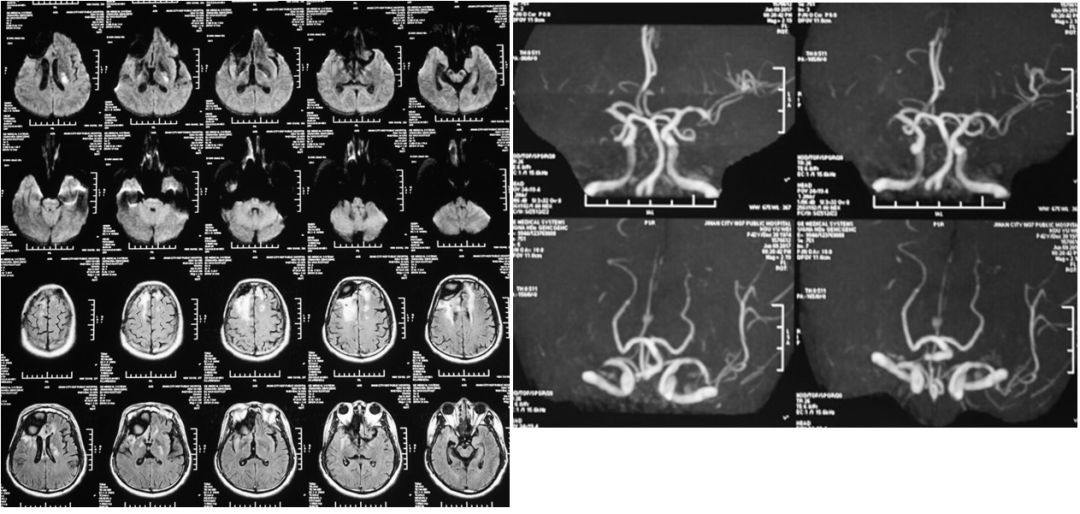

2017年6月与9月颅脑MR